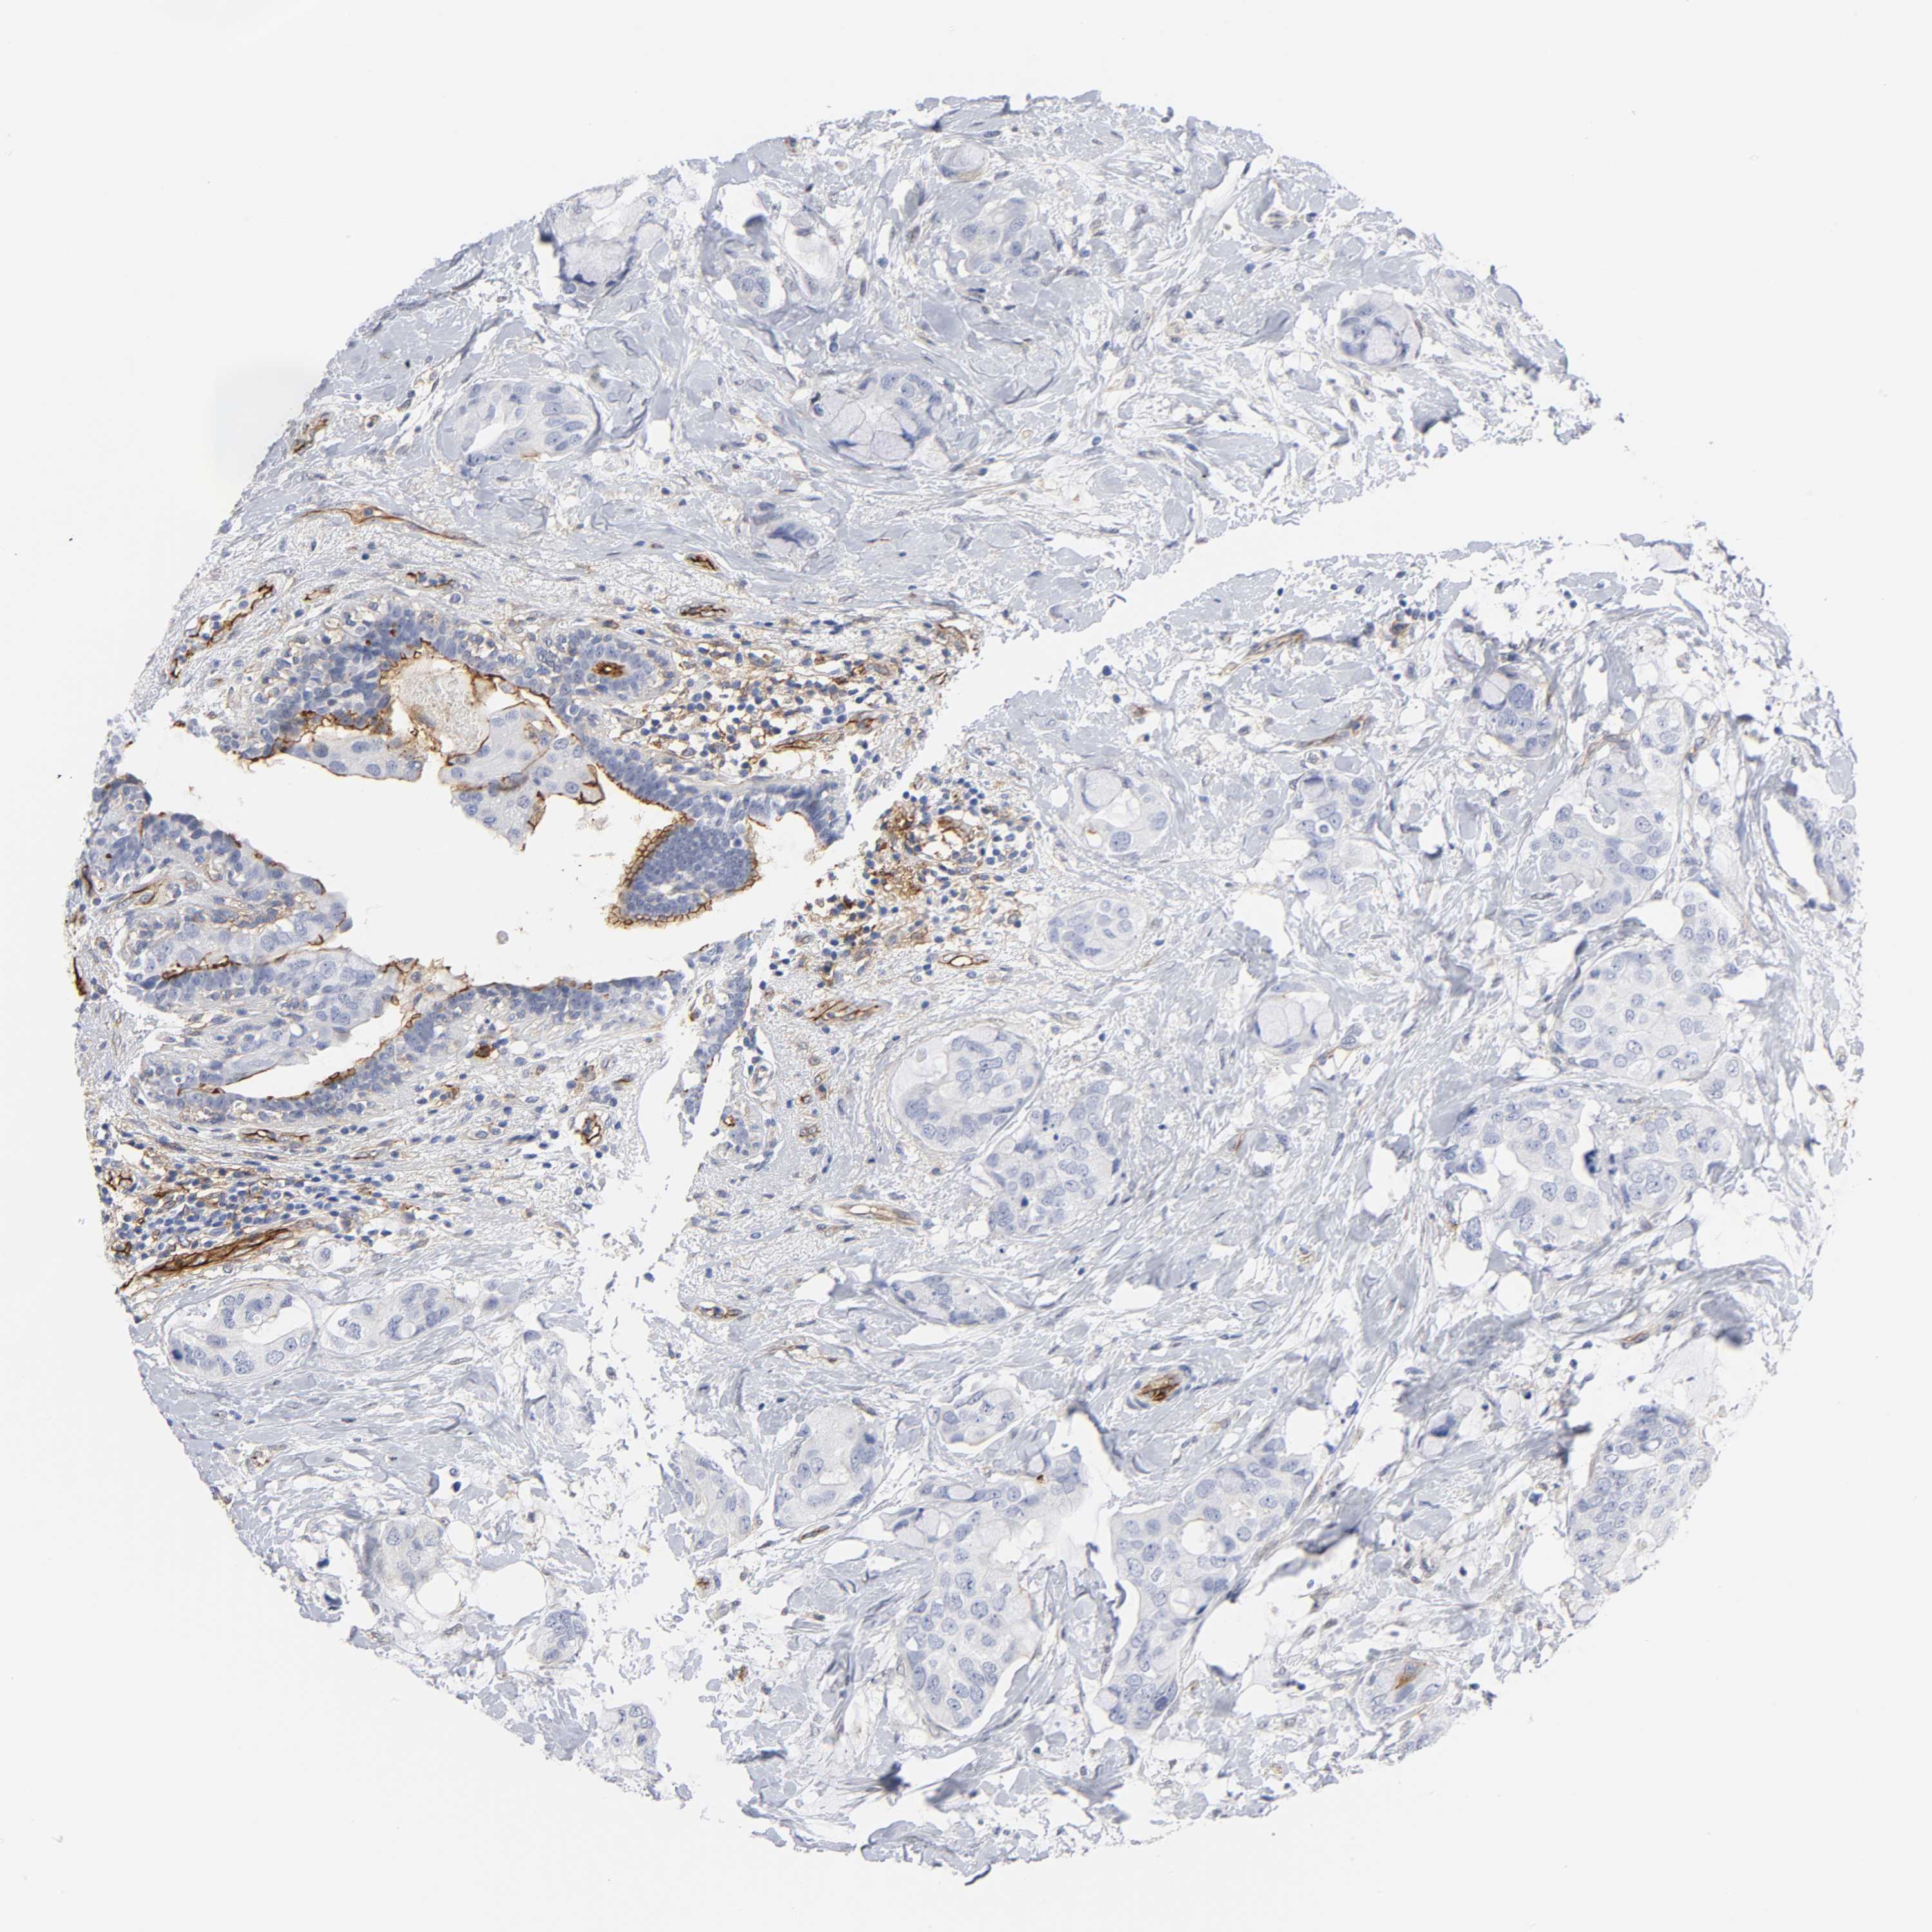

CANCER BREAST CANCER Show tissue menu

BRCA TCGA BRCA VALIDATION PROTEIN EXPRESSION